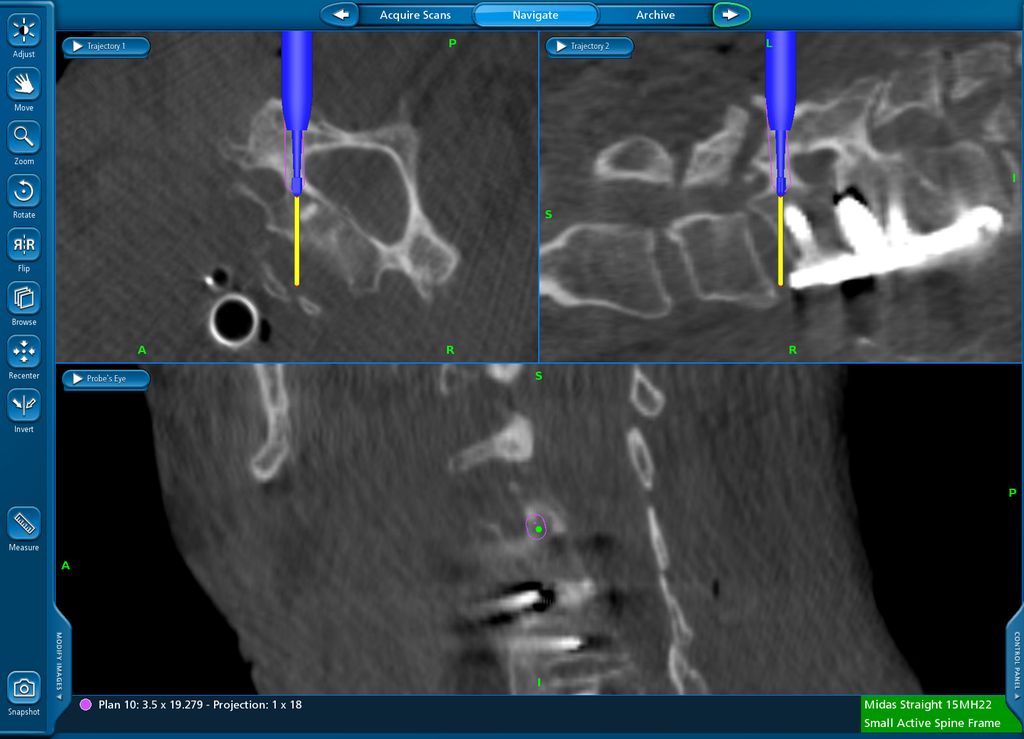

Beispiel für die Implantation zervikaler Pedikelschrauben. In diesem Fall kam es bei einem 61-jährigen Patienten 10 Jahre nach anteriorer zervikaler Diskektomie und Fusion (ACDF) C4/5 und ventraler Verplattung C4–6 zu einer Ankylosierung auch von C6/7. Nach Sturz kam es zu einer Fraktur bei C6/7 mit begleitender Bogenfraktur und auch Beteiligung der dorsalen Ligamenta (Abb. 1 und 2). Klinisch bestanden ausgeprägte Nackenschmerzen und kein neurologisches Defizit. Es wurde die Indikation der dorsalen Verschraubung von C4 auf Th1 gestellt. Intraoperativ wurde routinemäßig zusätzlich eine kleine Referenzschraube in einer Lamina – entfernt von der Dornfortsatz-Referenzklemme für die Navigation – gesetzt. Mit dieser konnte intraoperativ die Genauigkeit der Navigation exakt überprüft werden (Abb. 4 und 5). Mittels navigierter High-Speed-Fräse wurden die Schraubenkanäle vorgebohrt (Abb. 6), im Anschluss wurde der Bohrkanal ausgetastet und die Schrauben wurden implantiert. Abbildung 7 zeigt eine Röntgenkontrolle 3 Monate postoperativ.

Abb. 4: Screenshot der Navigationssoftware intraoperativ (Stealth Station S7). Es erfolgt die intraoperative Verifizierung der Navigationsgenauigkeit mittels kleiner Schraube in der Lamina, positioniert idealerweise entfernt von der Dornfortsatz-Referenzklemme. Die navigierte Fräse wird im Situs exakt auf die Schraubenmitte gerichtet, und die Navigation bestätigt die Genauigkeit | |